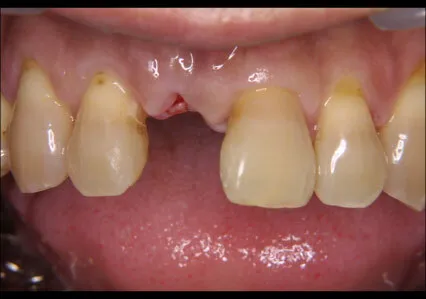

症例③

| 主訴 | 他院にて抜歯後、歯を入れたい |

|---|---|

| 診断名 | 歯根破折 |

| 年齢 | 46歳 |

治療に用いた装置(治療法) | 骨造成・インプラント |

| 部位 | 右上1 |

| 治療期間 | 8か月 |

| 治療費用 | 造成:55,000円 インプラント:462,000円 |

| リスク・副作用(治療に関する) | 腫服、しびれ |